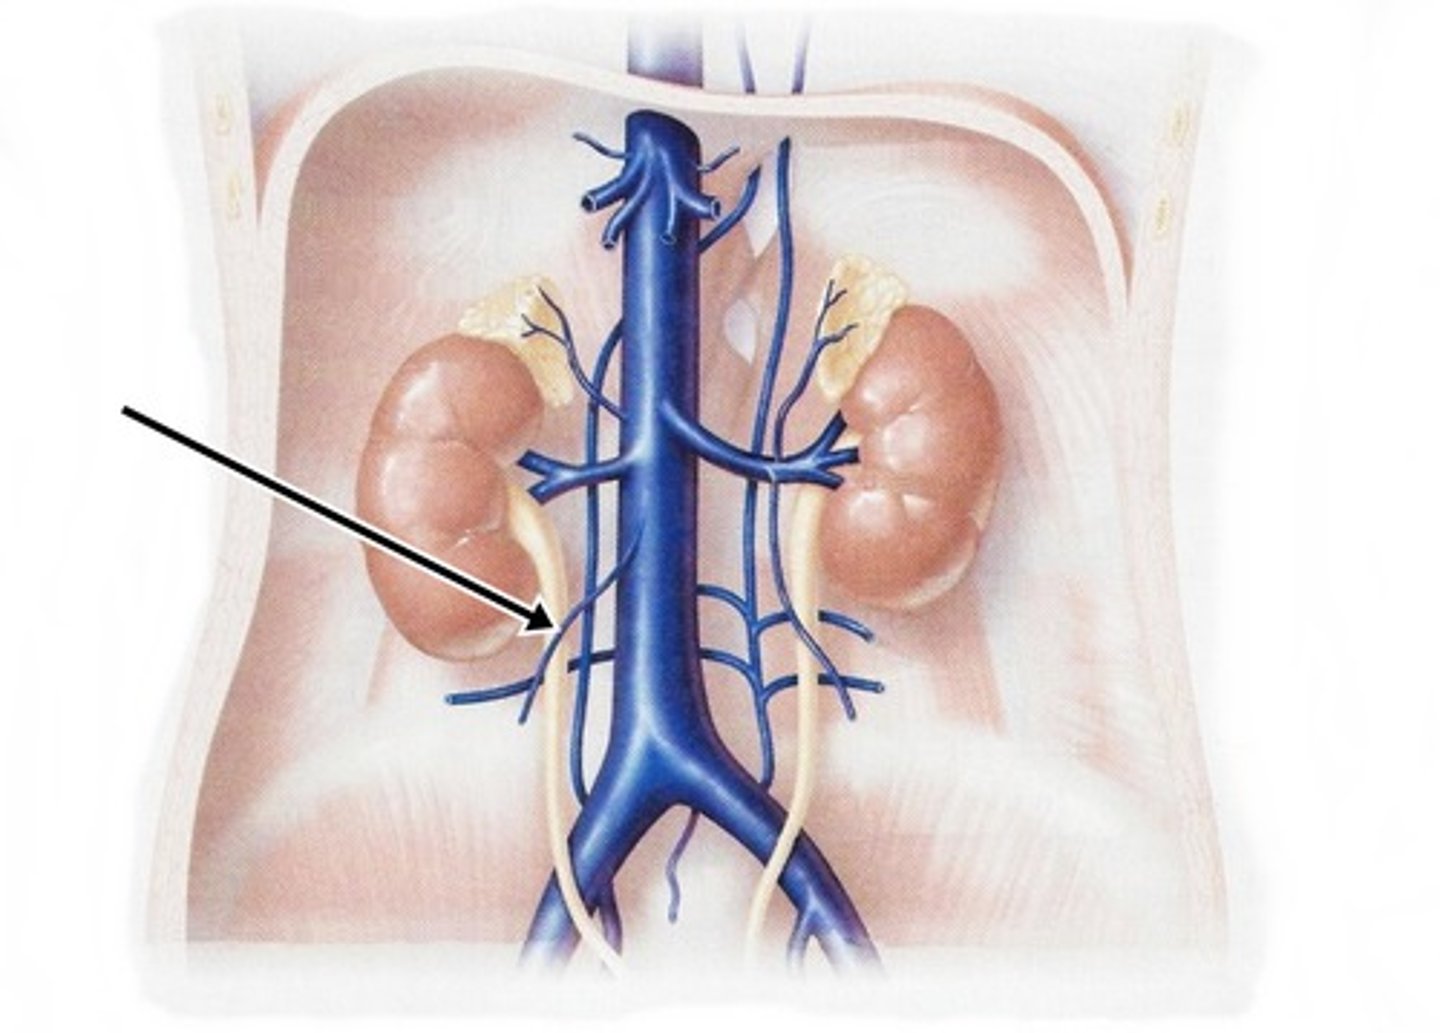

inferior vena cava

renal veins

left gonadal vein

right gonadal vein

common iliac vein